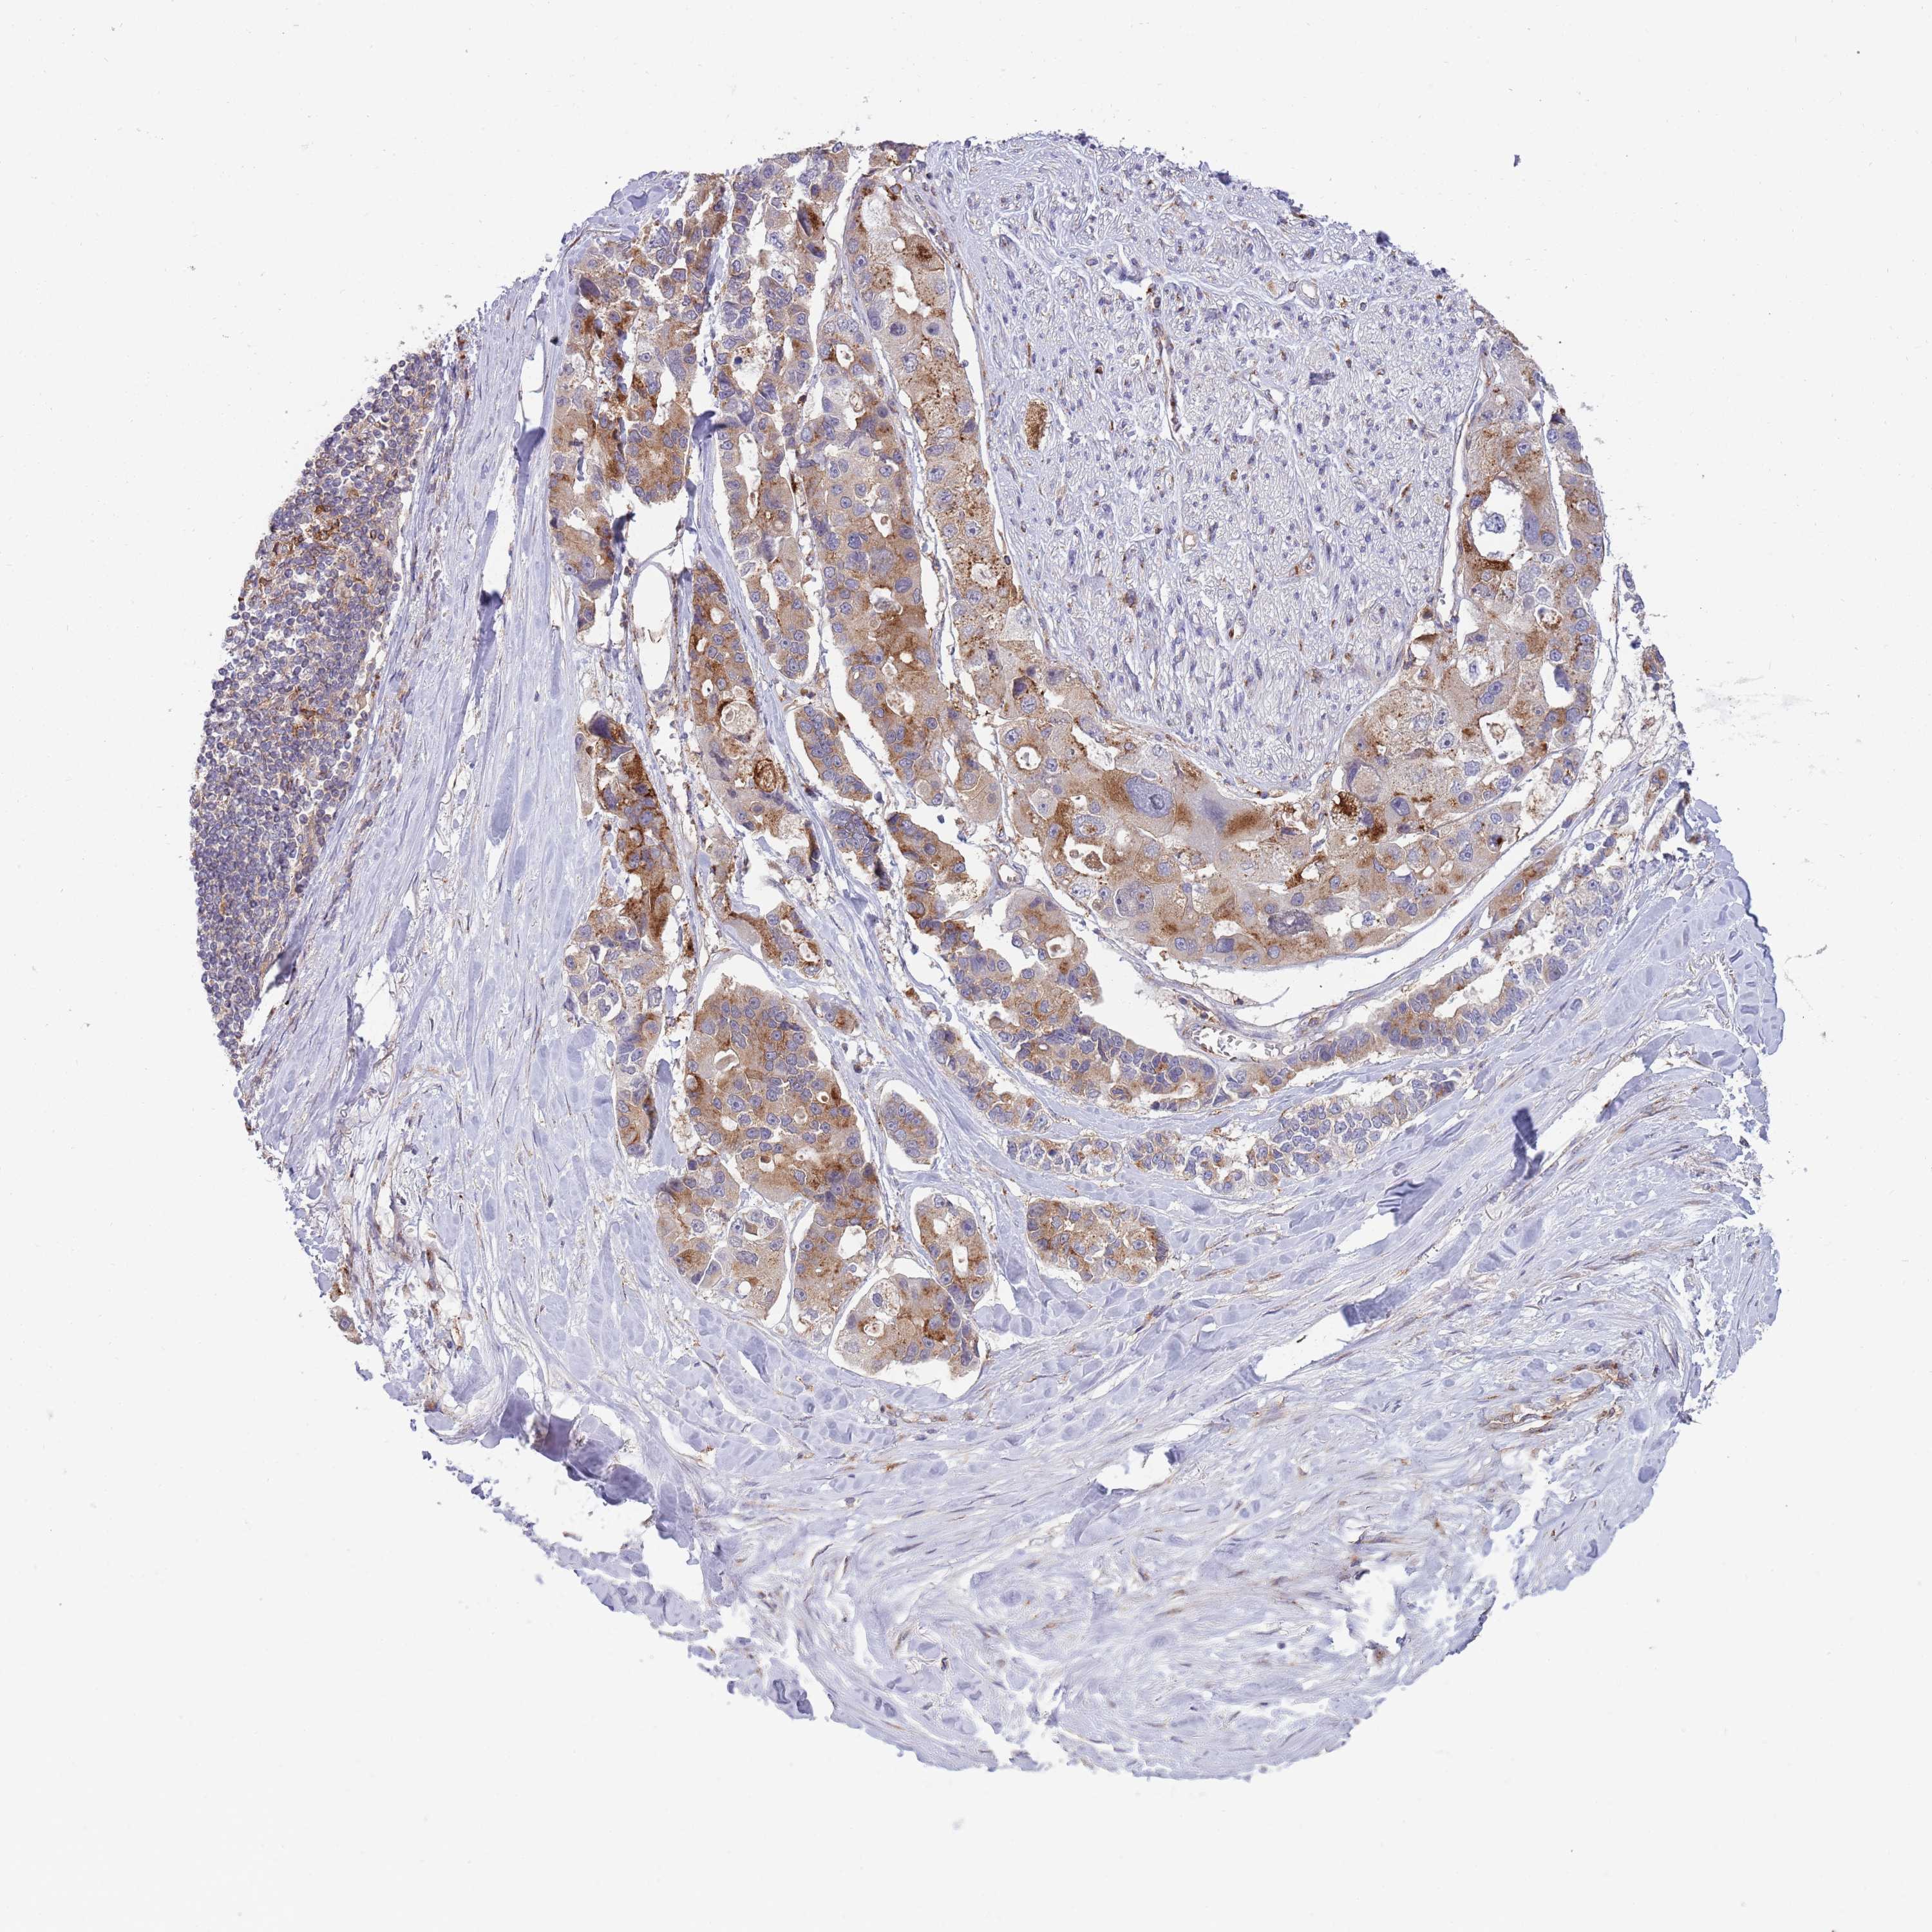

CANCER LUNG CANCER Show tissue menu

Lung cancer

Human cancer